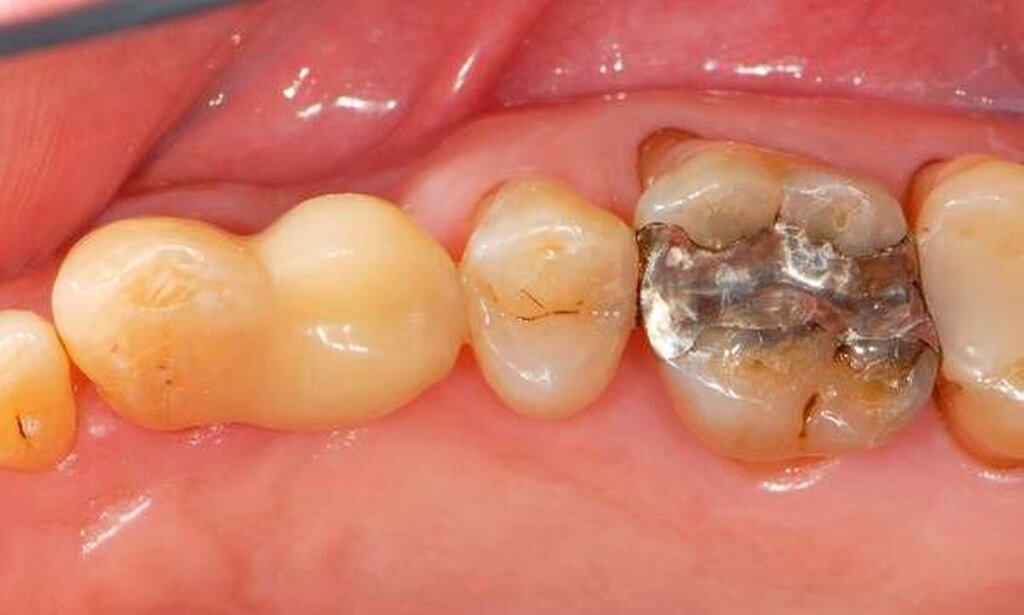

Abbildung 2: Direkte Teilüberkronung im Seitenzahnbereich (R1-Technik)

In den Abbildungen 1 bis 3 werden Optionen für frugale Interventionen auf restaurativem Sektor aufgeführt. Es handelt sich um direkte Vollüberkronungen im Frontzahnbereich (hier: hergestellt in R1-Technik / einphasig) (Abbildung 1), direkte Teilüberkronungen im Seitenzahnbereich (hier: hergestellt in R1-Technik / einphasig) (Abbildung 2), Reparatur-Restaurationen im Seitenzahnbereich (hier: hergestellt in R2-Technik / zweiphasig) (Abbildung 3). Technische Einzelheiten zur Vorgehensweise und den Ergebnissen sind an anderer Stelle beschrieben (Literatur siehe oben).

Für die in Abbildung 2 dargestellte Situation eines tief zerstörten Prämolaren gelten ähnliche Charakteristika. Es gibt in der restaurativen Zahnheilkunde viele Neuerungen, die das Behandlungsspektrum vergrößert haben. Dazu zählen unter anderem:

ein- oder zweiphasiges Vorgehen je nach Defektausdehnungen (R1- und R2-Technik),

von Präparationsgrenzen unabhängige Verschalungstechniken, die auch bei nicht-kariesbedingten Zahnhartsubstanzschäden (wie etwa Hypomineralisationen) zum Einsatz kommen können,

schadensgerechte Reparaturtechniken (Abbildung 3),

neuartige Insertionstechniken, die unter anderem die Anpassung neuer Restaurationen an vorhandene prothetische Versorgungen (Reziproktechnik) erlauben.